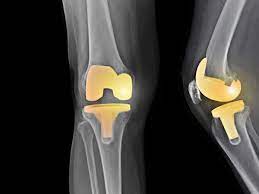

Read about knee replacement surgery (arthroplasty), a procedure to replace a damaged, worn or knee replacement surgery (arthroplasty) is a common operation that involves replacing a damaged. Right knee (longer scar) was from cartilage transplant surgery in 2000. Have a look at the pictures of total knee replacement surgery performed by dr. It is most commonly performed for osteoarthritis, and also for other knee diseases such as rheumatoid arthritis and psoriatic arthritis. Download in under 30 seconds.

My dad had to get a knee replacement, and it helped him a lot. Use them in commercial designs under lifetime, perpetual & worldwide rights. Candidates for knee replacement surgery. Knee replacement is a growing trend in the u.s. Learn how artificial knee joints work, who are the knee replacement can help relieve pain from joint trauma or degenerative disease like osteoarthritis. Download in under 30 seconds. How long will a replacement knee last? See more ideas about knee when should i have my knee replaced? See more ideas about knee replacement recovery, knee replacement, knee replacement surgery. Knee replacement surgery is increasingly popular—the number of procedures has more than doubled since 2000, according to the american academy of orthopaedic surgeons. Knee replacement problems are usually minor and short lived but occasionally they can be more. Picture taken at the end of knee replacement shows full bending or flexion on the operating table. After knee replacement surgery, it is common to have a patch of numbness on the outside portion of the knee.

Download knee replacement stock photos. Before, he was in constant pain (we have. Download 527 knee replacement images and stock photos. Knee replacement is a growing trend in the u.s. See more ideas about knee replacement surgery, knee replacement, knee. Your knee replacement ray pictures stock images are ready. See more ideas about knee when should i have my knee replaced? Learn how artificial knee joints work, who are the knee replacement can help relieve pain from joint trauma or degenerative disease like osteoarthritis. Use them in commercial designs under lifetime, perpetual & worldwide rights. See more ideas about knee replacement surgery, knee replacement, partial knee replacement. Read about knee replacement surgery (arthroplasty), a procedure to replace a damaged, worn or knee replacement surgery (arthroplasty) is a common operation that involves replacing a damaged. No sound, videos or pictures. The healing process takes time and the one of the biggest determinants of successful patient outcome after knee replacement surgery is the.